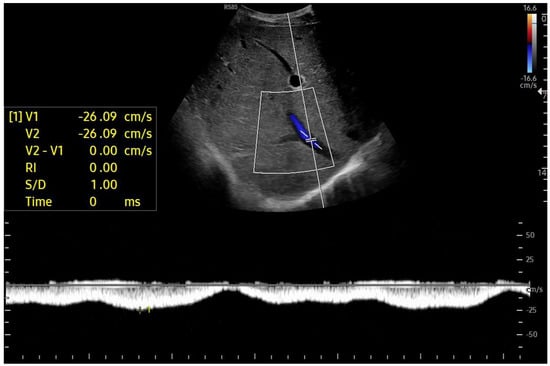

Doppler patterns in Fontan patients resemble those observed in chronic liver disease, including reduced portal flow velocity (mean flow velocity < 14 cm/s) [56]. The Fontan procedure inevitably alters hepatic venous waveforms on Doppler US (Figure 10, Figure 11, Figure 12 and Figure 13). Inverted portal flow has a specificity of 100% for diagnosing PHTN [57] (Figure 12). The hepatopetal phase pattern in the hepatic vein differs between patients with total cavo-pulmonary anastomosis (including both lateral tunnels and extracardiac conduits) and those with atrio–pulmonary connection [58,59,60]. In atrio–pulmonary connection, hepatopetal flow is preserved (Figure 10), reflecting the exclusion of atrial contribution to venous circulation, whereas in total cavo-pulmonary anastomosis, flow reversal (Figure 11) occurs only during early expiration. Similarly to congestive heart failure, hepatic veins and the IVC are dilated, with abnormally increased hepatic vein pulsatility, regardless of the anastomosis technique [54,61,62]. The loss of the normal three-phase Doppler pattern in hepatic veins is universal following bi-cavo-pulmonary surgery due to the absence of atrial contraction. The presence of a monophasic pattern indicates advanced liver injury [63].

Figure 10.

Doppler Ultrasound of the middle hepatic vein showing the loss of the normal three-phase pattern due to the absence of atrial contraction.

Among individuals with Fontan physiology, the hepatic veins typically show a dampened, predominantly hepatopetal monophasic waveform, reflecting the presence of long-standing hepatic congestion. Venous flow velocities are markedly reduced compared with those measured in healthy individuals [63,64]. In contrast, in later stages characterized by cirrhosis and increased hepatic stiffness, further dampening or paradoxical changes in the venous flow pattern may be observed [37,56,64].

In particular, the hepatic venous Doppler waveform offers valuable insight into hemodynamic changes over time. In the early post-Fontan period, in the absence of atrial contraction and before structural liver damage is evident, the hepatic venous flow may display a relatively blunted monophasic or biphasic waveform with reduced phasicity, reflecting the lack of pulsatility and elevated central venous pressure [37,56,64].

As FALD progresses, and especially in the setting of developing cirrhosis, the Doppler waveform may become more dampened or even flat, corresponding to the increasing stiffness of the hepatic parenchyma, reduced compliance of the vascular bed, and worsening portal hypertension [37,56,64]. Simultaneously, the hepatic veins may appear dilated in the early and mid-stages of disease due to chronic venous congestion, but may show reduced caliber in later stages as fibrosis progresses and vascular remodeling occurs [37,56,64].